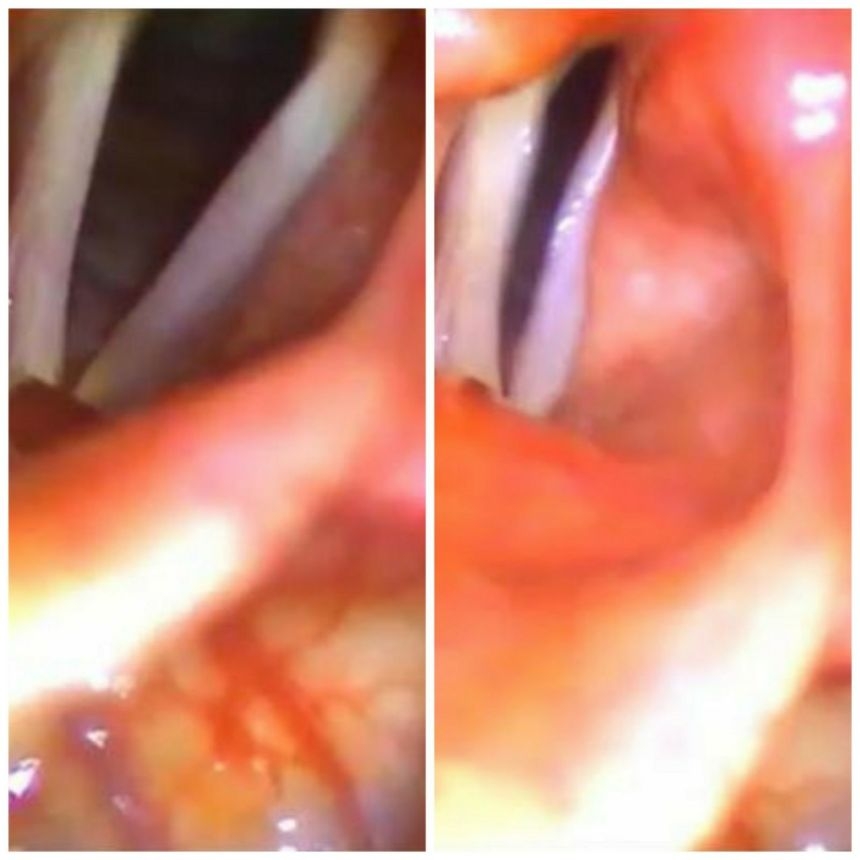

Tek taraflı ses teli felcinde ilişkili ses problemlerinin tedavisi için kullanılan ana yöntemler ses terapisi, enjeksiyon laringoplasti (ses tellerine dolgu yapılması, kapalı ses teli cerrahisi) ve tiroplastidir (açık ses teli cerrahisi). Bunlardan hangilerinin kullanılacağı ve zamanlaması hastanın klinik durumuna ve aspirasyon (boğaza sıvı kaçma) düzeyine göre değişebilir. Ses teli felci sonrası en erken dönemde yapılan doğru uygulamalar ile en iyi ses sonuçları alınabilmektedir.